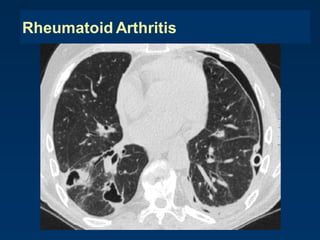

Rheumatoid Arthritis

Honeycombing – collagen vascular diseases

 rheumatoid arthritis and scleroderma

 almost indistinguishable from UIP due to IPF

 associated findings, typical of the disease, may help in the

differential diagnosis